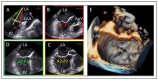

Mitral regurgitation (MR) is a common valvular heart disease associated with significant morbidity and mortality. For patients at high or prohibitive surgical risk, mitral transcatheter edge-to-edge repair (M-TEER) offers a less invasive alternative to surgery. This review outlines key aspects of patient selection and procedural planning for M-TEER, with a focus on clinical and echocardiographic criteria essential for success. Comprehensive imaging-especially 2D and 3D transesophageal echocardiography-is critical to assess leaflet anatomy, coaptation geometry, and mitral valve area. Selection criteria differ between primary and secondary MR and are guided by trials such as COAPT and MITRA-FR. Optimal outcomes rely on careful screening, anatomical suitability, and multidisciplinary evaluation. With growing experience and advancing technology, M-TEER has become a transformative option for treating severe MR in non-surgical candidates.